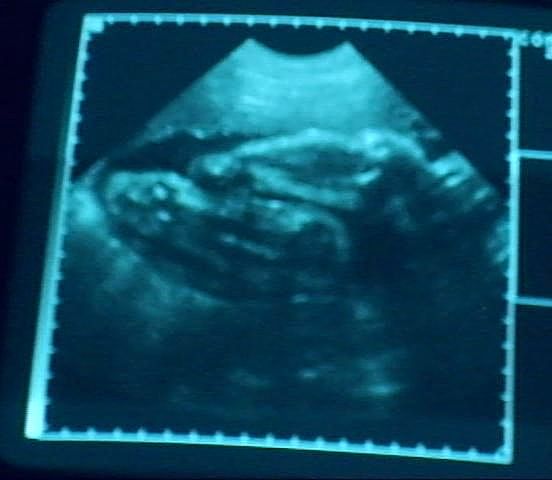

2D Ultrahangok ('07 július - '08 x, Baja)

32+5 Babalábak #2 (08/01/15)